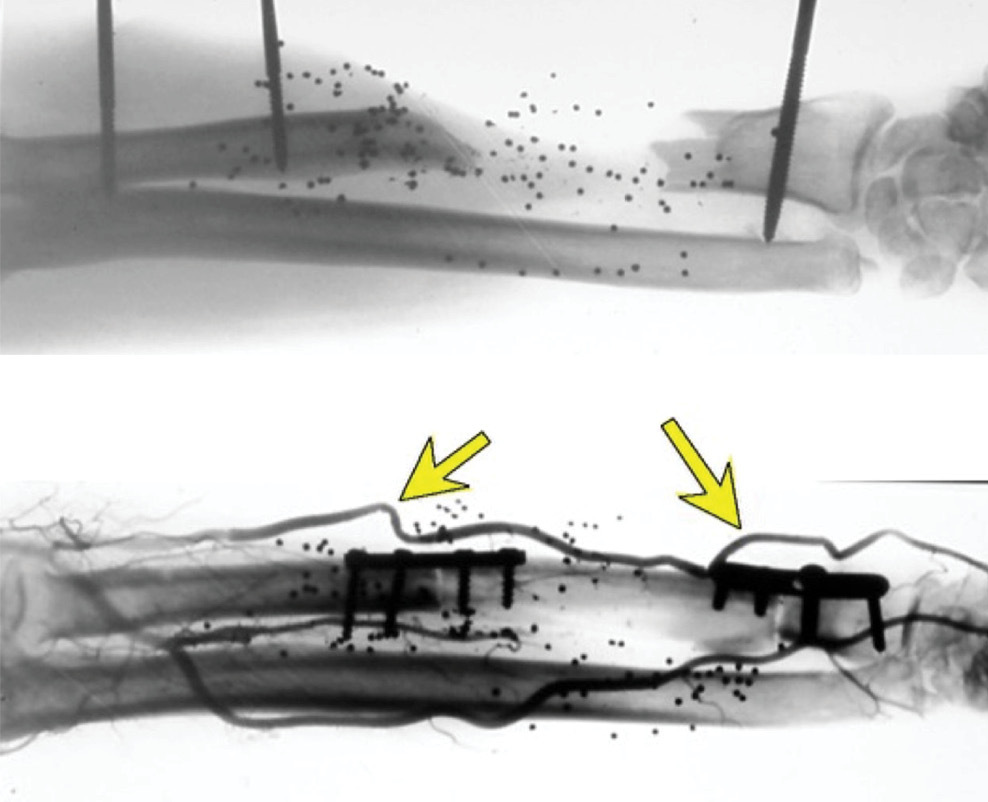

The study was performed in 66 fresh cadaver limbs. The contribution to the fibula, skin and adjacent soft tissues from the peroneal and anterior tibial vessels was examined using (i) India ink injection and bone histology, and (ii) lead oxide radiography of their vascular anatomy.8

These studies revealed a reliable blood supply to the proximal epiphysis and the proximal two-thirds of the diaphysis from the anterior tibial artery (Figure 8A). The branches to the epiphysis from this artery were provided by the recurrent genicular artery and several short vessels arising from the anterior tibial as it passed forward beneath the tibiofibula joint (Figure 8D). Although the peroneal artery provided the dominant supply to the shaft of the bone via its nutrient and musculoperiosteal branches, its contribution to the head of the fibula was scanty (Figure 8B). Finally, the vascular anatomy to the leg was examined in 100 clinical angiograms revealing 21 limbs with anomalies, including two cases with a peronea magna (Figure 9).